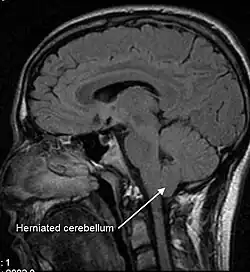

An untreated CSF leak can result in coma or death as late stage findings as the brainstem herniates through the skull base or foramen magnum .[36][34]

Low CSF volume can cause the cerebellar tonsil position to descend, which can be mistaken for Chiari malformation; however when the CSF leak is repaired the tonsil position often returns to normal (as seen in upright MRI) in this "pseudo-Chiari" condition.[58] A further, albeit rare, complication of CSF leak is transient quadriplegia due to a sudden and significant loss of CSF. This loss results in hindbrain herniation and causes major compression of the upper cervical spinal cord. The quadriplegia dissipates once the patient lies supine.[59] An extremely rare complication of sCSFL is third nerve palsy, where the ability to move one's eyes becomes difficult and interrupted due to compression of the third cranial nerve.[60]